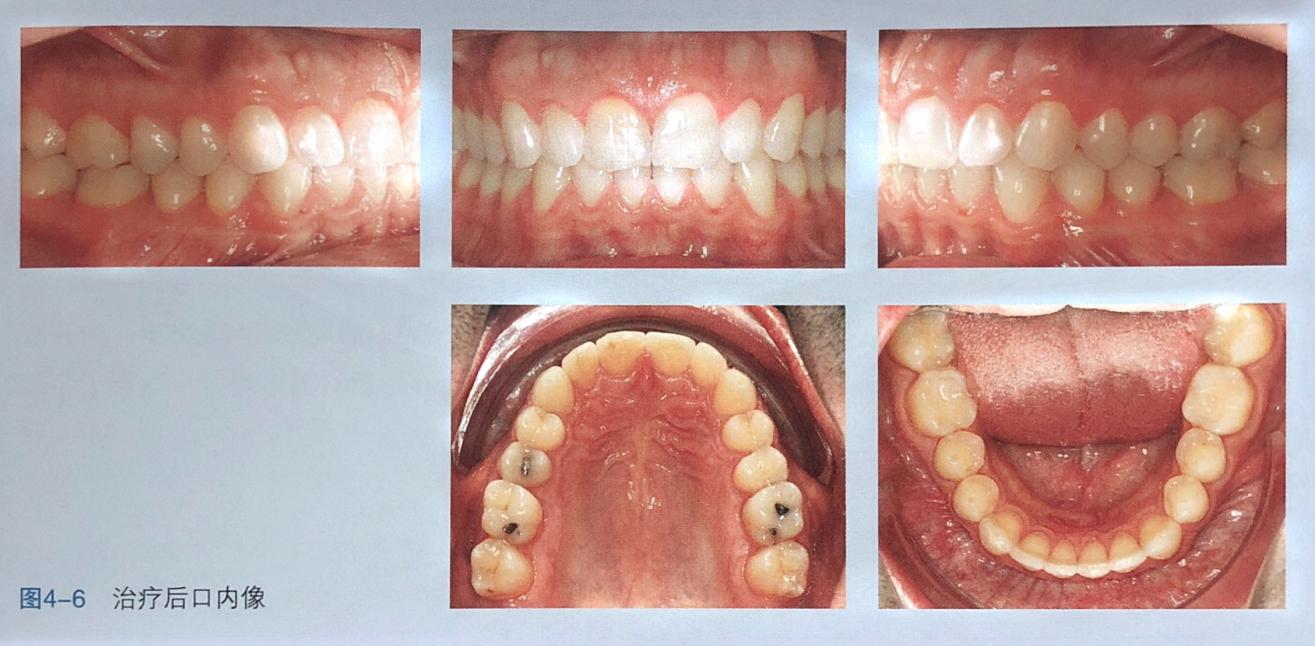

从图中可以看出黑三角和上中切牙间隙已重合上中切牙压根以正轴,其他方面也全部完成。